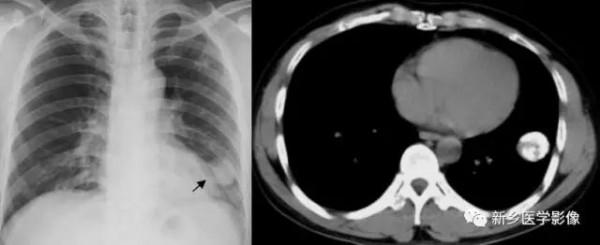

滲出性病變X線及CT影象

胸部X線正位片(a)示左肺紋理增多、模糊;CT肺窗(b)和縱膈窗(c)示兩下肺片狀高密度影,邊緣模糊。